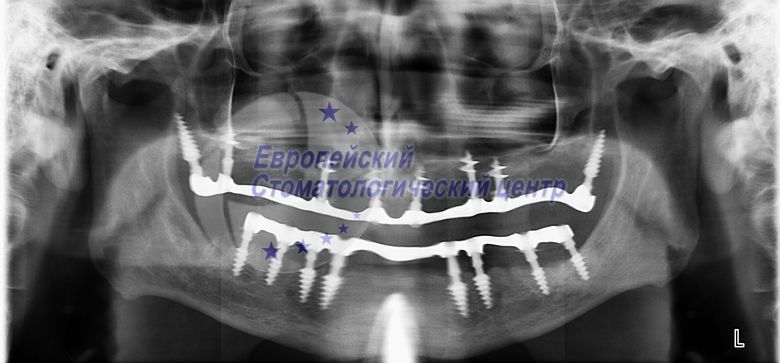

ОЗУ через два роки після операції